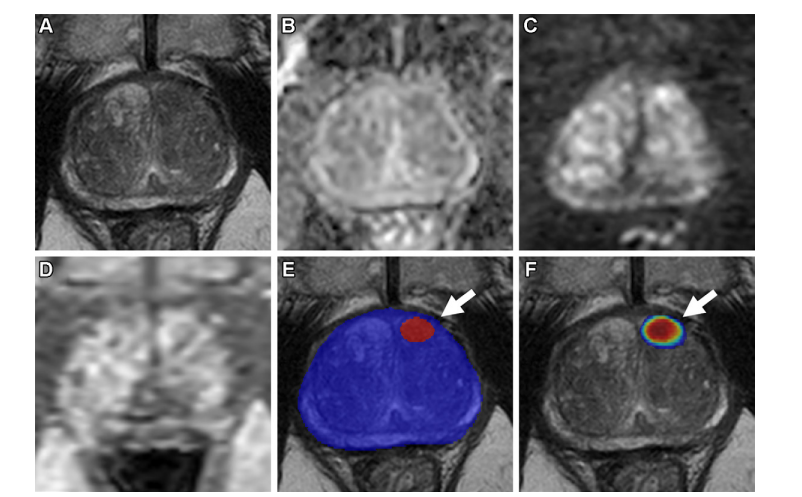

Figure 5 illustrates axial multiparametric MRI scans conducted on a 69-year-old male participant with a serum prostate-specific antigen level measured at 7.3 ng/mL. The imaging findings included: (A) a T2-weighted image demonstrating tissue characteristics, (B) an apparent diffusion coefficient map highlighting water diffusion properties, (C) a high-b-value diffusion-weighted image with b = 1500 sec/mm² emphasizing nerve fiber integrity, (D) a dynamic contrast-enhanced image showing vascularity over 54 frames captured at 5.6-second intervals, (E) a T2-weighted image overlaid with an AI prediction map where red contour indicates positive predictions and blue contour delineates AI-aided prostate organ segmentation, and (F) a T2-weighted image displaying an AI probability map with red shading denoting higher likelihoods. Within these scans, one lesion was flagged by the AI algorithm within the left midgland anterior transition zone (indicated by an arrow in both E and F images), which was identified as a false positive based on radiologist-verified ground truth. A biopsy sample obtained from this site, located in the left midgland medial region, confirmed benign findings.

图5展示了69岁男性的轴向多参数MRI扫描结果:(A)T2加权图像显示前列腺组织特征;(B)表观扩散系数图提示细胞间空隙;(C)高b值扩散加权图像显示微粒转移特征;(D)动态对比增强图像显示腺体边缘模糊;(E)AI预测图覆盖区域显示腺体形态;(F)AI概率图显示各区域风险等级分布。系统性活检报告发现左侧腺体内部有异常结构需进一步评估。